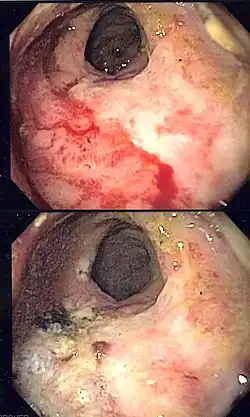

| Endoscopic image of radiation associated vascular ectasias (RAVE) before and after therapy with argon plasma coagulation. | |

Endoscopy is the mainstay of diagnosis for radiation damage to the rectum, with either colonoscopy or flexible sigmoidoscopy. RAVE is usually recognized by the macroscopic appearances on endoscopy characterized by vascular ectasias.[8] Mucosal biopsy may aid in ruling out alternate causes of proctitis, but is not routinely necessary and may increase the risk of fistulae development.[6] Telangiectasias are characteristic and prone to bleeding.[3] Additional endoscopic findings may include pallor (pale appearance), edema, and friability of the mucosa.